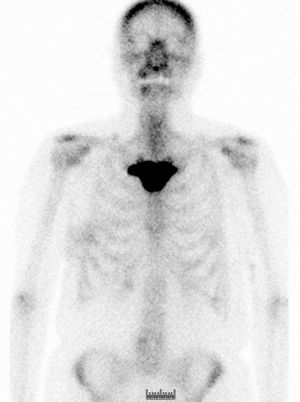

The study of the extension of the disease included BS, which revealed the presence of a diffuse blastic lesion in the sternal manubrium, suggestive of Paget's disease or a metastatic lesion (Fig. 1). The study was completed with radiographs of chest, lumbosacral spine and pelvis (Figs. 2 and 3), in which the only finding was increased density in L4-L5 facet joints. Chest CT, recommended by the professionals in nuclear medicine, revealed sclerosis in the sternal manubrium, suggestive of metastasis (Fig. 4).